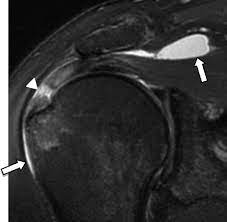

what is primary shoulder impingement ?

structural narrowing of the subacromial space, leading to mechanical compression of the rotator cuff tendons/ bursa

extrinsic impingement syndrome

hooked acromion (type iii)

ac joint osteophytes (bone spurs)

thickened coracoacromial ligament

what is secondary impingement ?

functional instability of the GH joint, due to poor neuromuscular control/ instability, leading to mechanical compression of the rotator cuff tendon, subacromial bursa and long head of biceps tendon.

what are factors contributing to secondary impingement

GH joint instability = humeral head migrates superiorly due to labral injuries, capsular laxity and repetitive overhead movements, compression the subacromial structures

scapular dyskinesis = abnormal motion , position and stability of scapular, which leads to poor acromion positioning, reducing subacromial space

muscle imbalances/weakness = weakness of rotator cuff = less humeral head control. weakness of scapula stabilzes = functional narrowing of subacromial space during motion

symptoms of shoulder impingement

diffuse pain around acromion (overhead movements )

tightness in inferior and posterior joint capsule

pain within 70-120 degrees abduction

external rotators is weaker than internal rotators